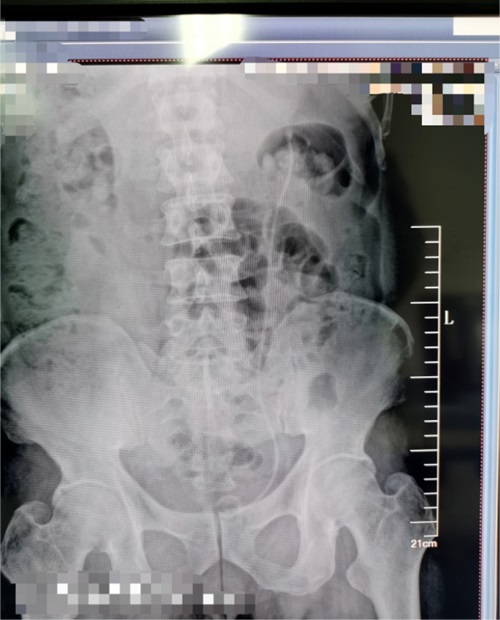

患者,男,61岁,主因“发现左肾鹿角形结石1月余”入院。泌尿系CT显示:左肾鹿角状结石;右肾结石。后在可控负压吸引下行输尿管软镜钬激光碎石术治疗肾结石。

术前示图如下:

术后6周复查泌尿系CT,左输尿管内支架置入术后,左肾结石基本消失